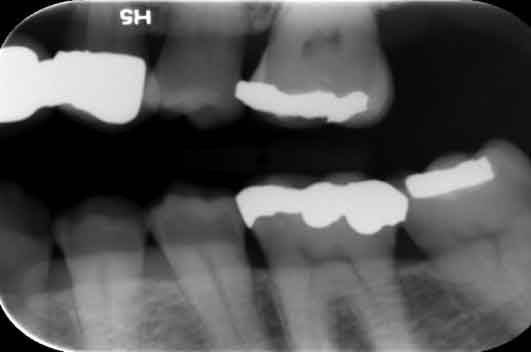

Return to "Modern Applications for The Cantilever Fixed Partial Denture" partial-denture-15b Next Previous